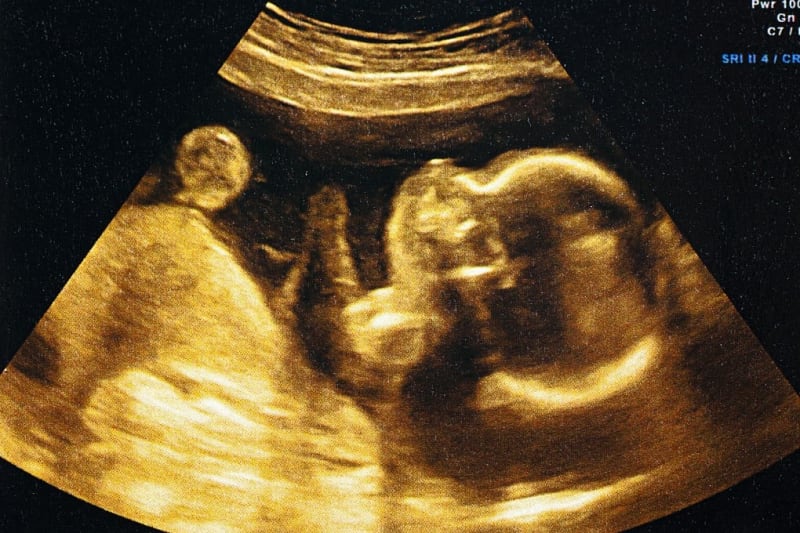

In a groundbreaking achievement, researchers from the Chinese Academy of Sciences have successfully built the world's first "mini-womb on a chip" that replicates how human embryos implant during early pregnancy. This remarkable innovation could unlock personalized fertility treatments for countless women struggling to start families.

What makes this achievement so exciting is its potential to transform fertility treatment. For the millions of women worldwide who face challenges getting pregnant, this technology could pave the way for personalized medical solutions tailored to their individual needs. The mini-womb system successfully recreates the key events that happen when an embryo implants and begins developing, giving researchers an unprecedented window into this delicate process.

The innovation centers around blastocysts, which are five to six-day-old embryos containing between 100 and 200 rapidly dividing cells. These tiny bundles of life include an outer layer that implants into the uterus to form the placenta and an inner core that eventually develops into a baby. The research team's model uses either actual human blastocysts or blastoids, cultured together with bioengineered human endometrial tissue they call an "endometrioid."